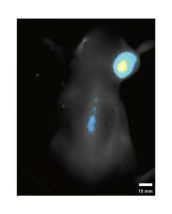

干细胞与免疫细胞追踪

动态追踪干细胞与免疫细胞在动物体内的迁移、归巢与分化过程,为细胞治疗研究给予关键数据支持。

bb95935f-c805-4197-877b-85a03cbc082e.png

干细胞追踪与脏器成像:实时观测细胞迁移与组织损伤